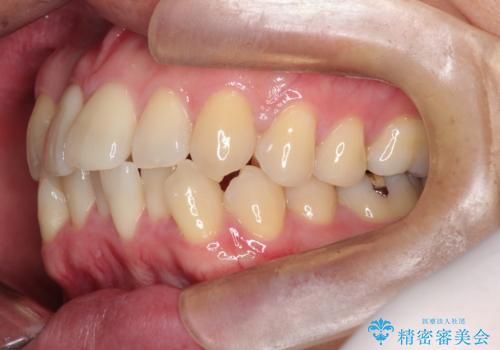

- 「歯のデコボコと前歯が引っ込んでいるのを治したい」を主訴に来院された患者様です。

デコボコの量が多かったため上下左右4を抜歯してワイヤー矯正で治療を行いました。

正面から見たときに右上2が全く見えないくらい、右上2が後ろに引っ込んでいる状態でしたが綺麗に並べる事が出来ました。